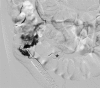

The aim of this study was to identify the frequency of rectosigmoidal involvement in patients with venous malformations (VM) of the lower extremities and to demonstrate multidisciplinary therapeutic options. The medical records and magnetic resonance images (MRI) of patients with VM of the lower extremities, over a six-year period, were reviewed retrospectively in order to determine the occurrence of rectosigmoidal involvement. Vascular interventions, surgical treatments, percutaneous and hybrid (endoscopy-guided angiography) sclerotherapy and procedural complications (according to Clavien-Dindo classification) were also noted. Of the 378 patients with vascular malformation of the lower limbs, 19 patients (5%) had documented venous rectosigmoidal malformation. All of these 19 patients reported episodes of rectal bleeding, while seven patients (36.8%) also had anemia. All patients underwent endoscopy. By endoscopy, seven patients (36.8%) showed discreet changes, and 12 patients (63.2%) showed pronounced signs of submucosal VM with active (47.3%) or previous (15.7%) bleeding. Treatment was performed in all patients with pronounced findings. Six patients underwent endoscopy-guided hybrid sclerotherapy, one patient underwent endoscopic tissue removal, one patient received percutaneous sclerotherapy and one patient received a combination of transvenous embolization and hybrid sclerotherapy. Three patients required open surgery. No complications occurred after conservative treatments; however, one complication was reported after open surgery. None of the treated patients reported further bleeding and anemia at the end of the follow-up period. In this cohort, rectosigmoidal VM occurred in 5% of patients presenting with a high incidence of rectal bleeding. Percutaneous or endoscopy-guided hybrid sclerotherapy appeared to be a safe and effective alternative to surgery.